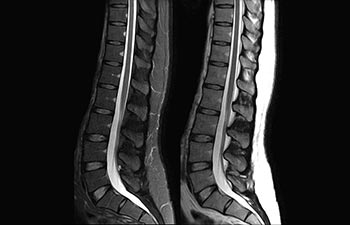

Up to 50% faster MR exams, so you can spend your time wisely

Find the right clinical applications for your needs